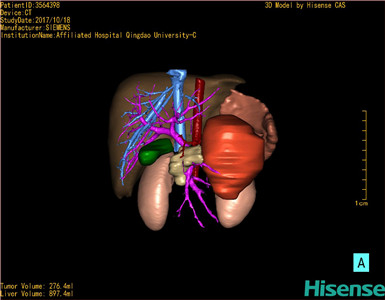

CT结果输入海信CAS系统后行3D重建及手术规划后,于2017-10-19全麻下行“胰体尾肿物切除术+脾切除术+大网膜切除术”手术治疗:

术前三维重建及手术方案设计:

将0.625mm双源薄层CT资料的静脉期和动脉期Dicom格式文件导入海信CAS系统。

通过调节窗宽窗位调整CT序号,对肝实质,胆囊,下腔静脉,肿瘤,肝动脉、门静脉及肝静脉等进行三维重建;系统自动计算肝脏体积。

模拟手术操作,自动计算切除肿瘤体积。肝脏体积为453.7ml,通过比对2-3岁正常肝脏体积为475.97±99.7ml,通过术前模拟手术,精准判断切除后剩余肝脏体积能耐受,避免肝衰竭发生。

术前三维重建:

重建图片